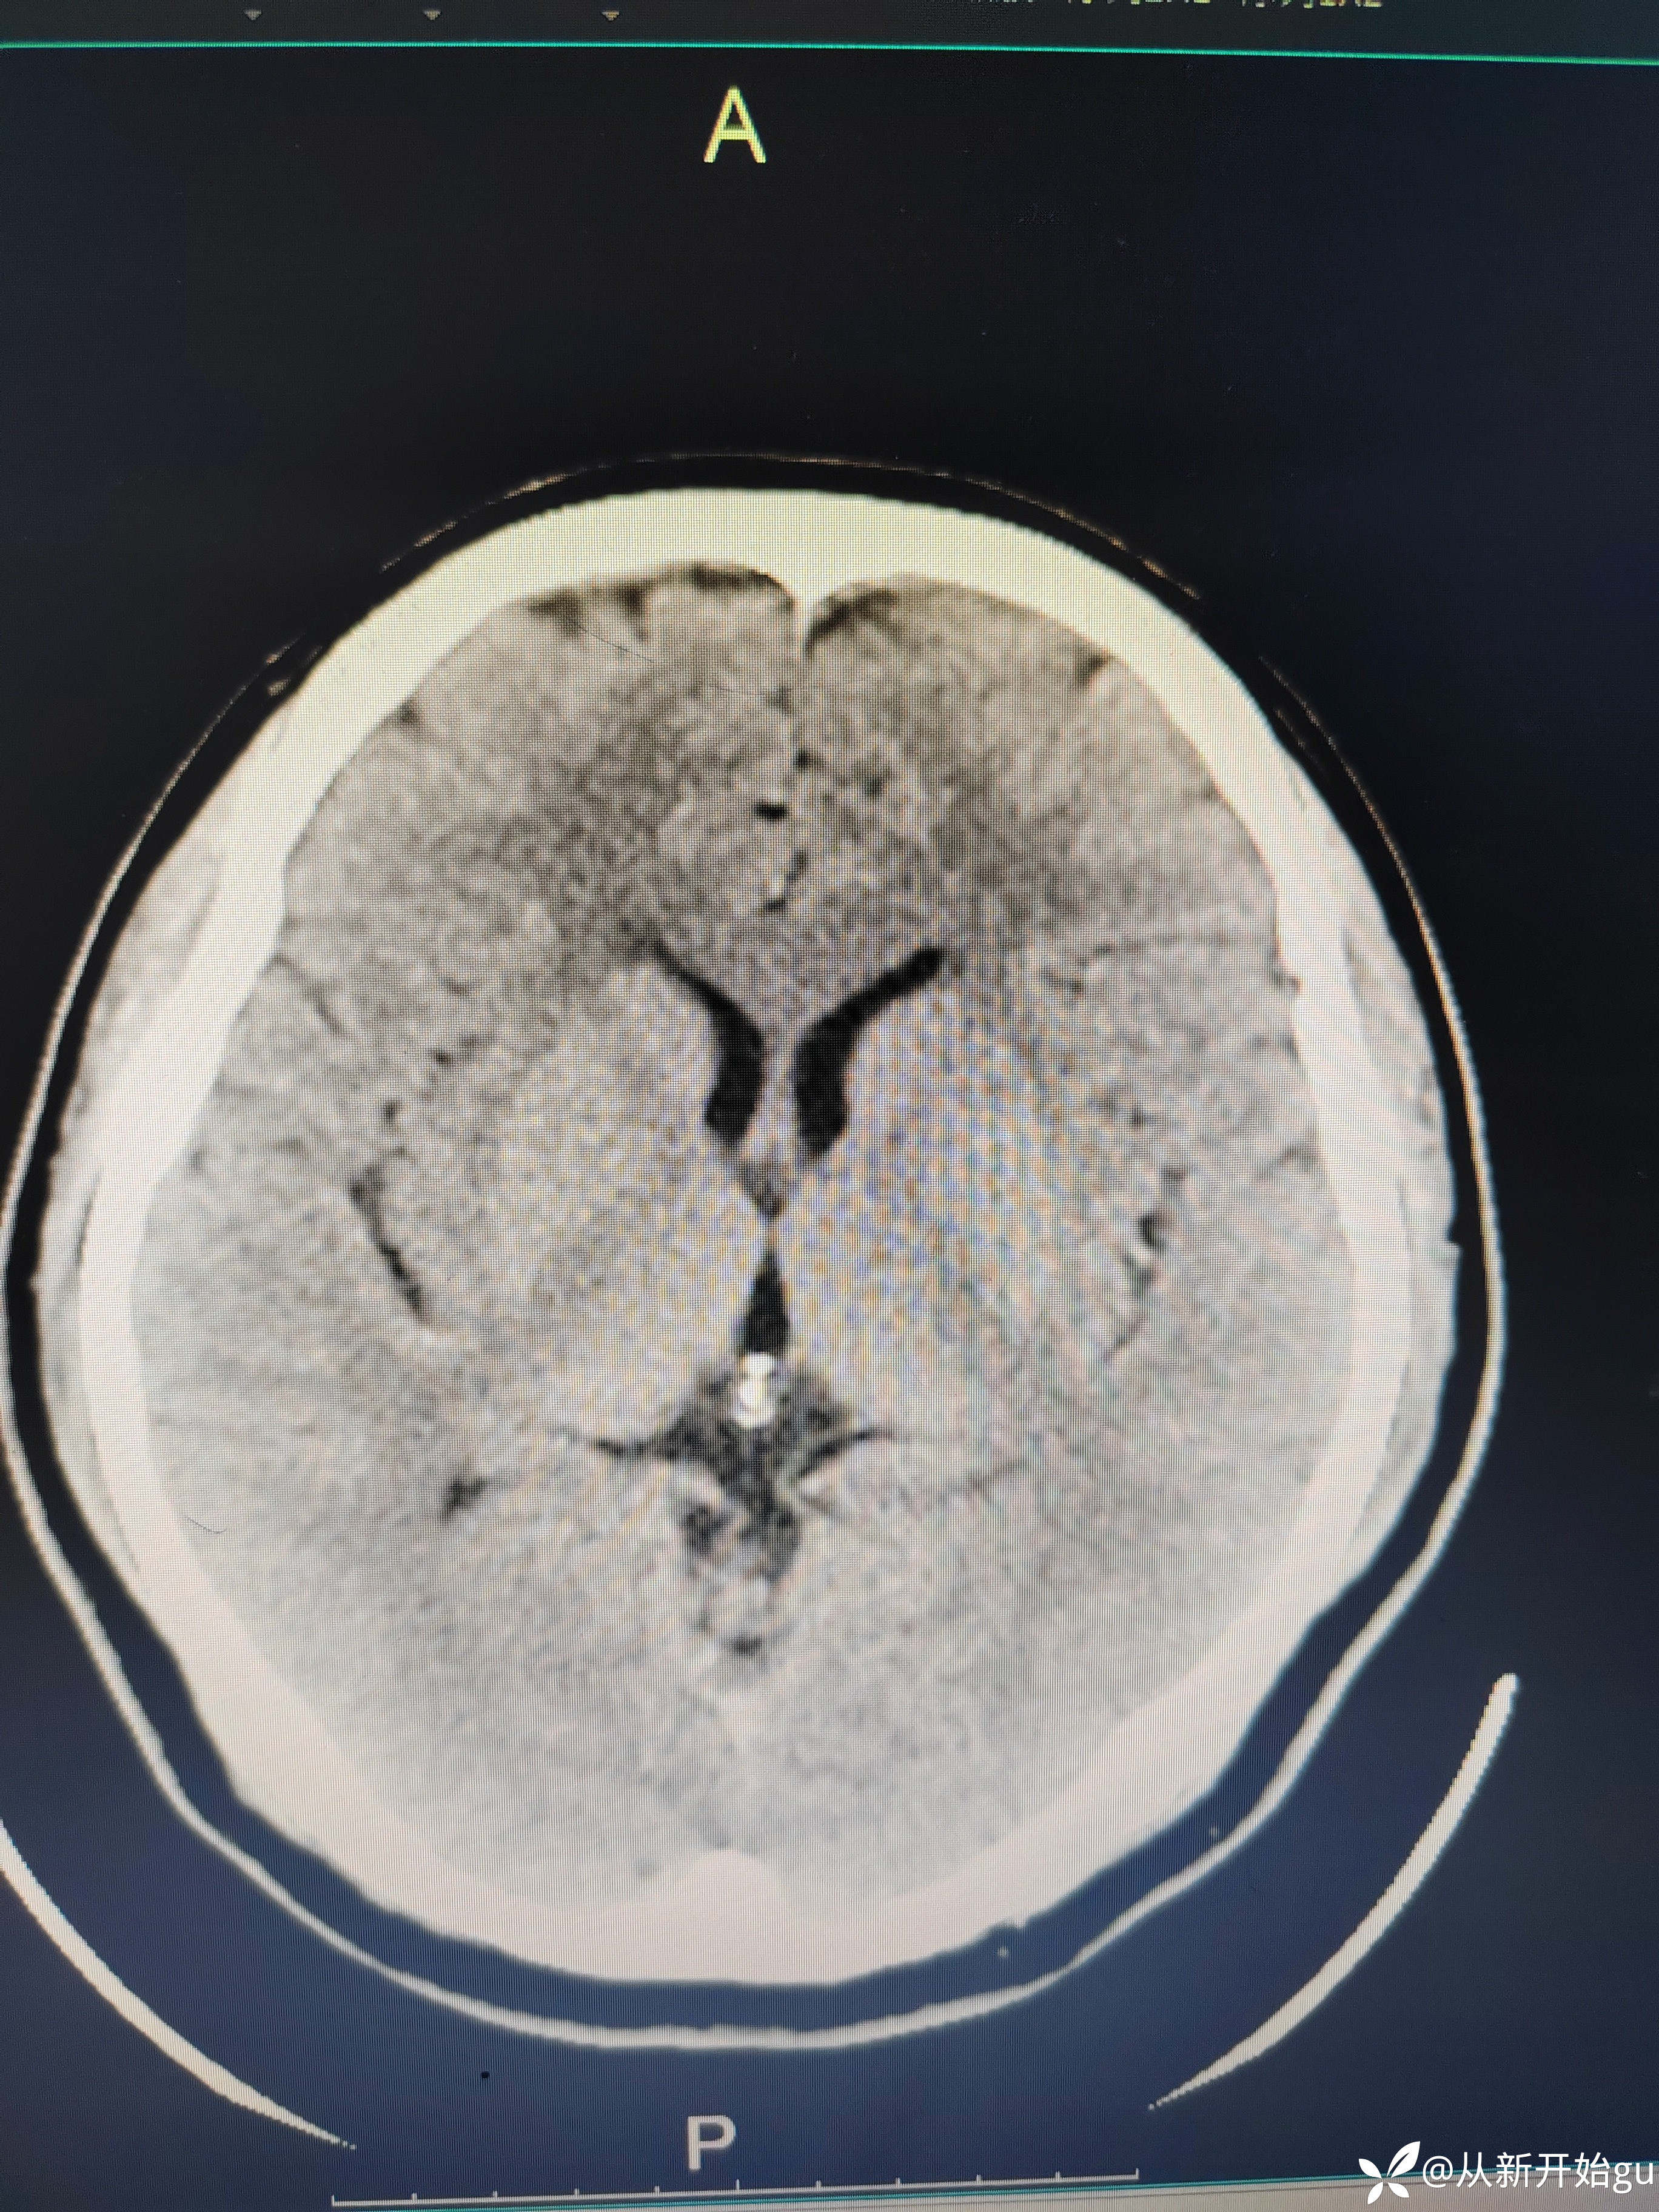

患者51岁男性,主因左下肢活动障碍1小时来院。既往高血压病史,查体,右侧鼻唇沟稍浅(家属诉之前就这样),神舌居中,左侧下肢肌力5级-,左侧跟膝胫试验欠稳准,左侧巴氏征阳性,评分也就一分,鼻唇沟稍浅未纳入。行颅脑CT检查如图所示